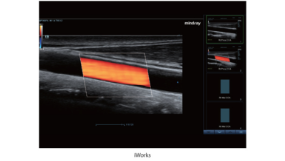

iWorks

iWorks memanfaatkan protokol pemindaian standar yang sudah tertanam di dalam untuk mendapatkan konsistensi yang lebih baik dan mengurangi waktu pemeriksaan hingga 50%. Fitur yang sangat fleksibel dan andal ini ditingkatkan lebih lanjut dengan kemampuan yang didefinisikan oleh pengguna.